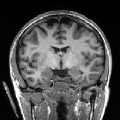

To compare the proposed approach to the mSENSE333SENSE reconstruction implemented by the Siemens scanner, software ICE, VB 17. one, Fig. 1 illustrates coronal anatomical slices reconstructed with both algorithms while turning off the temporal regularization in 4D-UWR-SENSE, so resulting in the so-called 3D-UWR-SENSE approach. Red circles clearly show reconstruction artifacts and noise in the mSENSE reconstruction, which have been removed using our 3D-UWR-SENSE approach. Comparison may also be made through reconstructed slices for and , as well as with the conventional acquisition (). This figure shows that increasing generates more noise and artifacts in mSENSE results whereas the impact on our results is attenuated. Artifacts are smoothed by using the continuity of spatial information across contiguous slices in the wavelet space. Depending on the used wavelet basis and the number of vanishing moments, more or less (4 or 8 for instance) adjacent slices are involved in the reconstruction of a given slice. For instance, using Symmlet filters of length 8 (4 vanishing moments) as in the conducted experiments here, 8 adjacent slices are involved in reconstructing a given slice. However, it is worth noticing that the introduced smoothing is anisotropic, in contrast to standard Gaussian smoothing that could be applied to anatomical data. Fig. 1 also compares 3D-UWR-SENSE and mSENSE reconstructed slices when applying additional spatial smoothing to the later with a mm3 Gaussian kernel. Comparisons clearly show that, even at such low spatial smoothing level, mSENSE images suffer from a significant blur. Moreover, the artifact present at for mSENSE (left red circle) is spread out but not fully removed by applying isotropic spatial smoothing.

Even for slice-selective acquisition schemes where the signal is supposed to be independent between adjacent slices, the proposed algorithm still allows us to exploit information continuity across slices which results from the imaged anatomy. Moreover, the smoothing level strongly depends on the regularization parameters that are used to set the thresholding level of wavelet coefficients. Images reconstructed using our algorithm present higher smoothing level than mSENSE without altering key information in the images. When carefully analysing the image background, one can notice the presence of motion-like artifacts that only affect the background and do not alter the brain mask. Such artifacts are nothing but boundary effects that are due to the use of wavelet transforms.